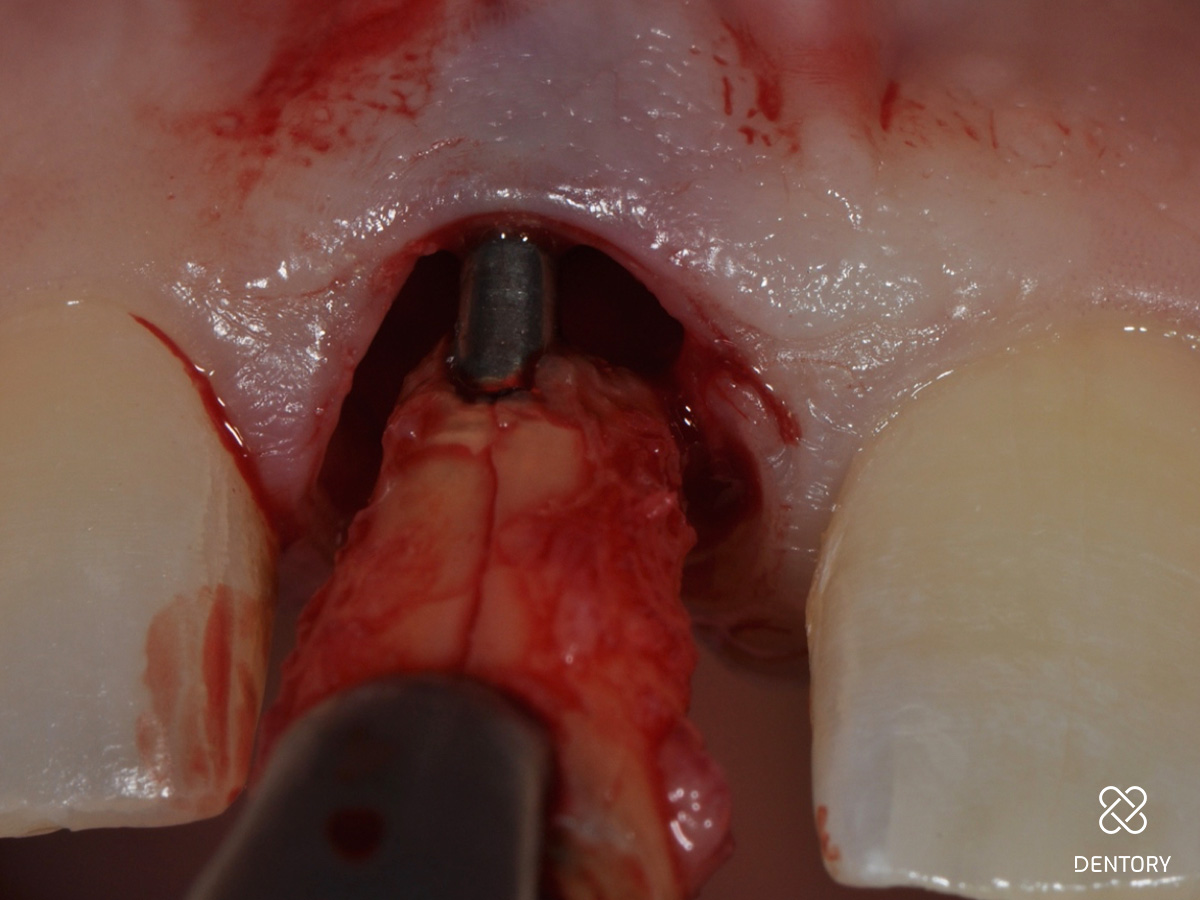

Abbildung 6

Nach der Extraktion sind die Längsfraktur der Wurzel und die deutlich apikale Positionierung des Wurzelstiftes erkennbar.